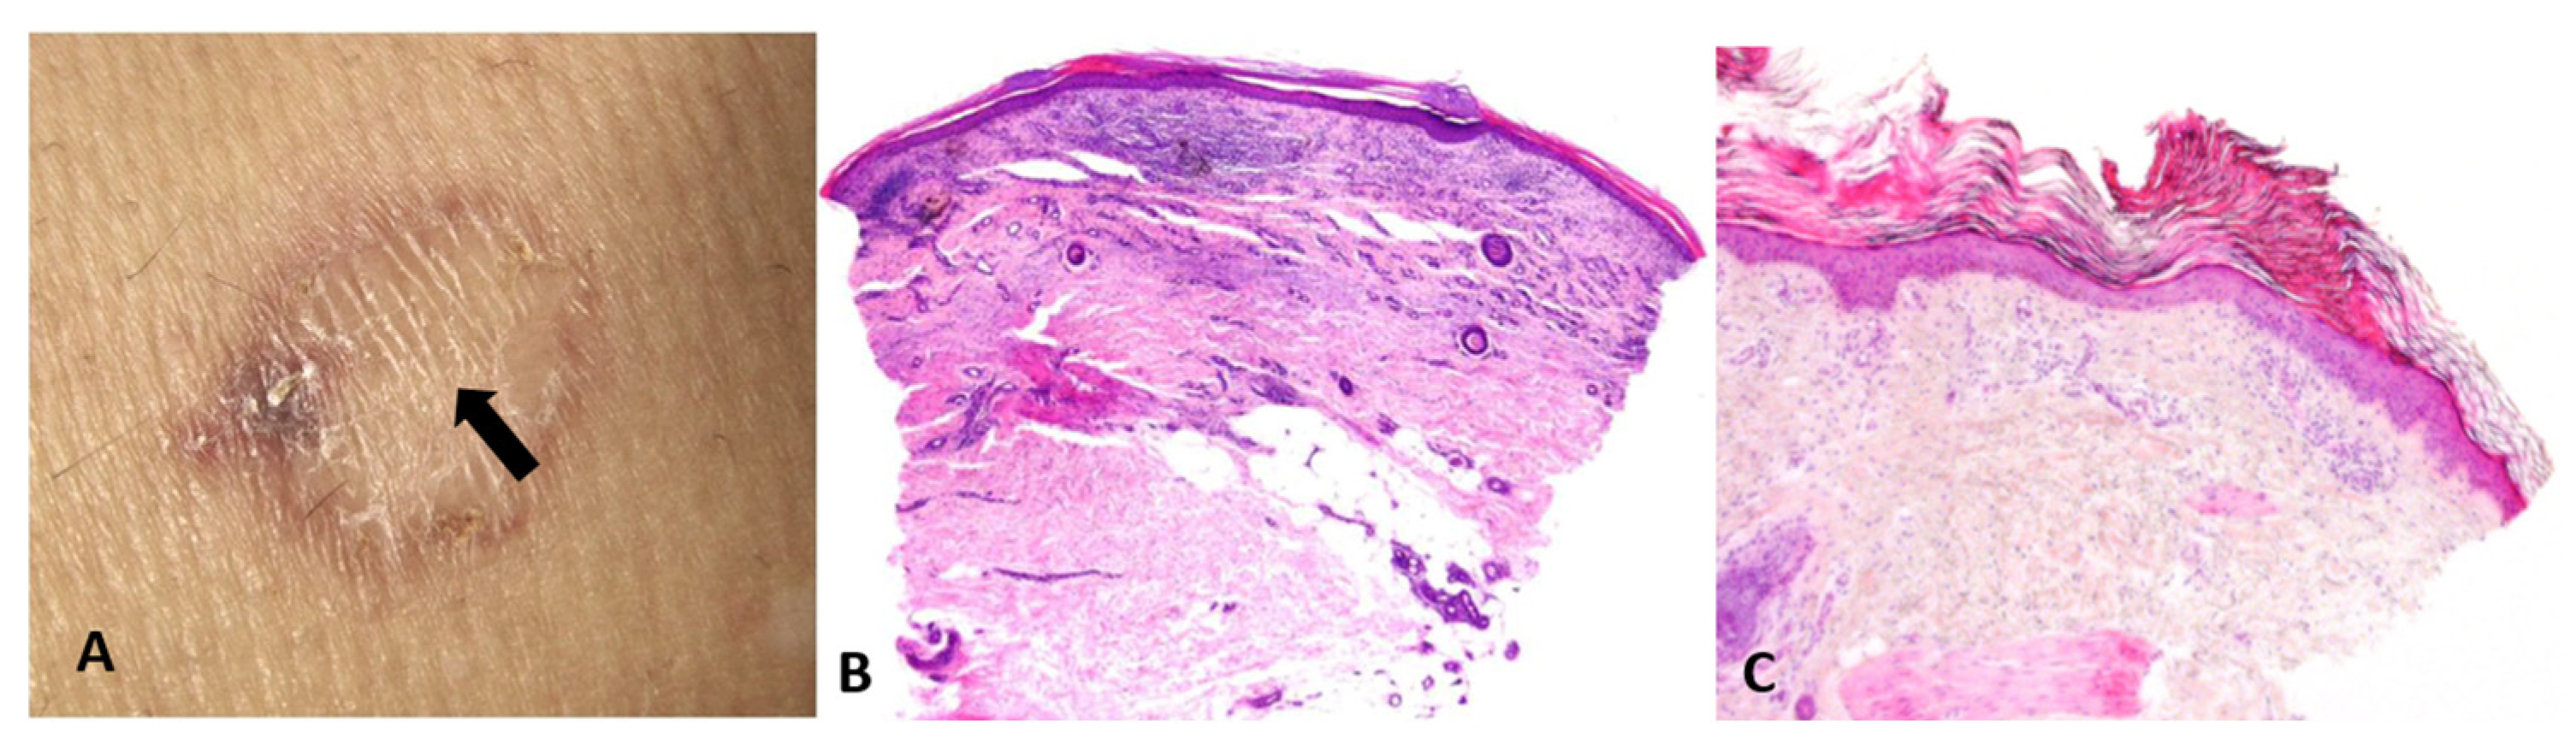

Base rates: When two hypotheses explain the finding equally well, the more common disease in the given setting (season, geography, clinic type) is preferred. However, always keep a rare “zebra” on the list if missing it would be catastrophic. For example, an atypical erythema multiforme-like eruption with a tendency to ulcerate may represent a primary cutaneous aggressive epidermotropic CD8+ cytotoxic T-cell lymphoma (Figure 2).

Figure 2.

(A) Primary cutaneous aggressive epidermotropic CD8+ cytotoxic T-cell lymphoma presenting with large, targetoid, partly ulcerated plaques resembling atypical erythema multiforme. (B) Vacuolar and lichenoid interface dermatitis-like changes. The condition was initially misinterpreted as atypical erythema multiforme, leading to diagnostic delay with a catastrophic outcome.